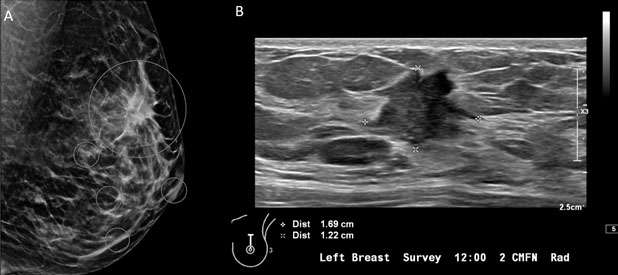

Mammography: Masses Figure 3

Figure 3: A) Mammography of the left breast with MLO view demonstrates irregular, spiculated mass in the left breast at 12 o'clock (big white circle). Additional calcifications in the left breast at 8 o'clock at anterior depth located 2 centimeters from the nipple, three additional groups of calcifications in the central and lower inner left breast are also suspicious (small white circles). B) Ultrasound of the left breast represents an irregular, spiculated hypoechoic mass, BI-RADS Category: 4C suspicious finding. Ultrasound guided biopsy was recommended and confirmed invasive ductal carcinoma, grade 2.